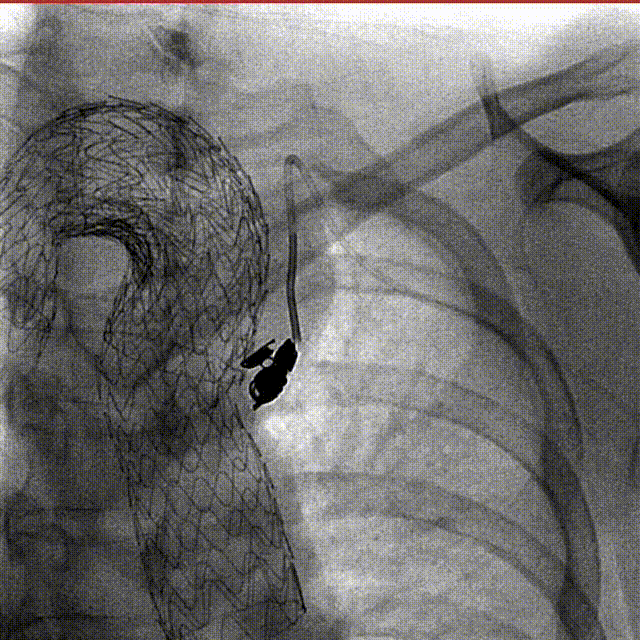

释放主体

技术优势:由于弓形陡峭,瘤腔巨大,支架需要硬导丝支撑到大弯侧,才能确保在释放时保持在原位不移动。

通过分段释放及办法,将支架远端先行释放,填塞瘤腔,可以提供更稳定的支撑力,确保在支架释放时的准确性。

远端释放之后,支架近端仍固定在输送杆上,可以在释放支架近端的过程中适当微调头端的位置。

gore医疗怎么样「胸有乾坤」化险为夷,通险畅机——GORE® TAG® 胸主动脉覆膜支架治疗累及异形弓部动脉瘤_https://www.jmylbn.com_新闻资讯_第20张

顶导丝让支架贴紧大弯侧血管壁

gore医疗怎么样「胸有乾坤」化险为夷,通险畅机——GORE® TAG® 胸主动脉覆膜支架治疗累及异形弓部动脉瘤_https://www.jmylbn.com_新闻资讯_第21张

分段释放支架